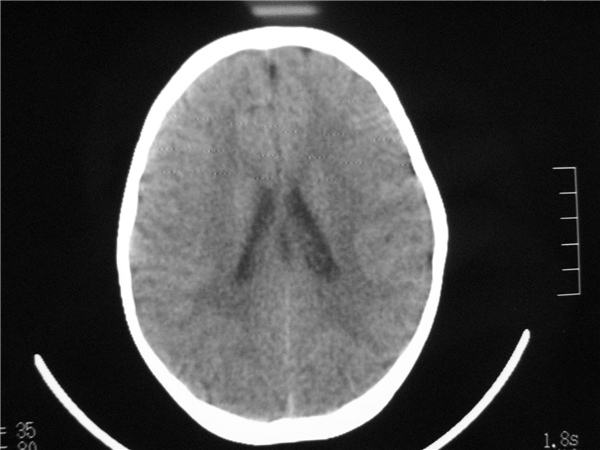

标题: PED2843: CT-23675 F 4Y 大家看看颅内有问题没。 [打印本页]

标题: PED2843: CT-23675 F 4Y 大家看看颅内有问题没。

四脑室扩大,三脑室稍扩大上移

胼胝体发育不全??

六脑室

四脑室扩大,,六脑室